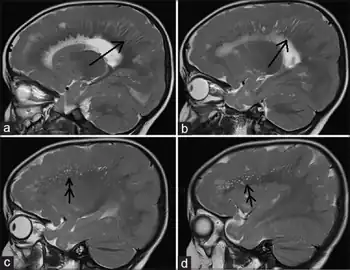

a, b)MRI shows radial stripes arrow c,d) show scattered dots in form of hyperintensities arrow

Different imaging modalities are commonly used for diagnosis. While computed tomography (CT) provides higher spatial resolution imaging of the brain, cerebral cortex malformations are more easily visualized in vivo and classified using magnetic resonance imaging (MRI) which provides higher contrast imaging and better delineation of white and gray matter.[7]

Diffuse pachygyria (a mild form of lissencephaly) can be seen on an MRI as thickened cerebral cortices with few and large gyri and incomplete development of the Sylvian fissures.[3]